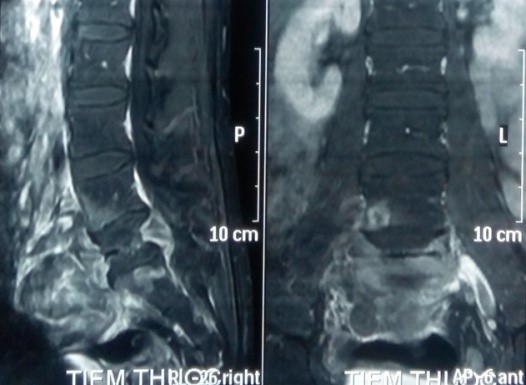

Trên X-quang, CT scanner khối u phá hủy vỏ xương gần hết thân và cuống sống L5.

Trên MRI, khối u giảm tín hiệu xâm lấn nhiều ra phía trước vào tiểu khung, xâm lấn ra phía sau chèn ép vào ống sống. Khối u ngấm thuốc mạnh, tăng sinh mạch nhiều trên phim MRI có tiêm thuốc.

CT scanner và MRI giúp đánh giá vỏ xương, tổn thương hủy xương cũng như mức độ thâm nhiễm quanh u. Trên T1W, T2W khối u TBKL đồng tín hiệu với tổ chức cơ, có thể giảm tín hiệu do collagen và hemosiderin, T1W sau tiêm ngấm thuốc. Phần mềm quanh u có thể hoại tử nhiễm trùng, đặc điểm này thường không gặp trong nang xương phình mạch, có thể để chẩn đoán phân biệt [5,11,12]. Bệnh nhân của chúng tôi, khối u phá vỡ thân đốt L5, thâm nhiễm phầm mềm rộng chèn ép ống sống phía sau, khối u cũng thâm nhiễm rộng ra phần mềm phía trước vào tiểu khung kích thước lớn khoảng 10 x 10cm, khối u đẩy lồi và một phần ôm lấy ngã ba chủ chậu ra phía trước gây khó khăn cho việc phẫu thuật lấy bỏ khối u và là yếu tố tiên lượng tái phát cao sau mổ.